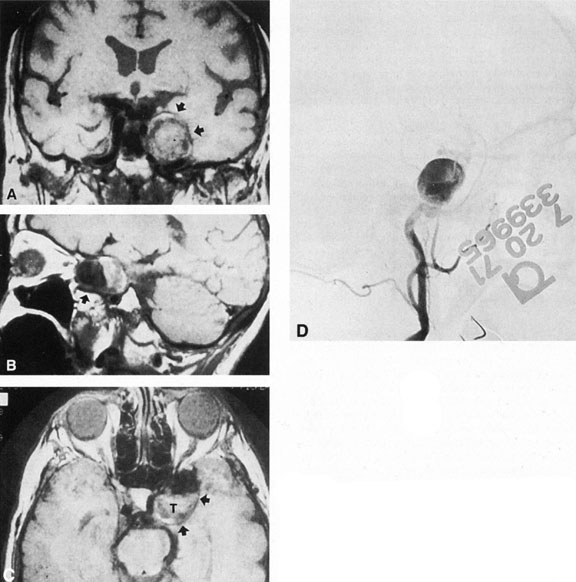

Intracavernous carotid aneurysms constitute only 2% to 3% of all intracranial aneurysms and are unique because of their location. These aneurysms arise from the internal carotid artery as it traverses the cavernous sinus4 (Fig. 3) and therefore produce a specific constellation of ocular and neurologic signs and symptoms. Rupture of such aneurysms, which are almost always saccular, may possibly result in carotid–cavernous sinus fistula, but subarachnoid hemorrhage is rare.5 However, slowly progressive enlargement is the rule, usually occurring within the cavernous sinus, with compression of the third, fourth, and sixth cranial nerves and later involving the first and second divisions of the fifth nerve (see Chapter 12).6 Progressive enlargement of the aneurysm forms a mass in the floor of the middle cranial fossa, compromising motor as well as sensory functions of the trigeminal nerve. Anterior expansion of the aneurysm erodes the anterior clinoid, optic foramen, and superior orbital fissure, eventually producing unilateral visual loss and exophthalmos. Posterior expansion, which occurs later, can erode the petrous portion of the temporal bone, causing ipsilateral facial palsy and, rarely, deafness. The sphenoidal sinus and the nasopharynx may infrequently be involved by inferior expansion and medial extension erodes into the sella and may simulate a pituitary tumor7 or cause bilateral ophthalmoplegia.8 Bilateral saccular intracavernous aneurysms occur uncommonly.9

Fig. 3. Magnetic resonance images of intracavernous aneurysm in a 72-year-old woman with left retrobulbar pain and sixth-nerve palsy. A: Coronal section (TR, 800 ms; TE, 30 ms). B: Parasagittal section (TR, 1000 ms; TE, 20 ms). C: Axial section (TR, 800 ms; TE, 30 ms). Note partial occlusion by thrombus (T). D: In a similar patient, carotid arteriogram (subtracted, lateral view) demonstrates a large intracavernous aneurysm.

Intracavernous aneurysms are suspected by the clinical presentation of a chronic cavernous sinus syndrome and are diagnosed by enhanced computed tomography (CT), magnetic resonance imaging (MRI), and arteriography (see Fig. 3). Because of the location and configuration within the cavernous sinus, direct surgical approaches to cavernous carotid aneurysms are hazardous. In recent years intravascular occlusion of the internal carotid by detachable balloon has evolved as a safe and successful procedure, often with relief of pain and improvement in ophthalmoplegia.10 Unfortunately, these balloons are commercially unavailable at the time of this writing.